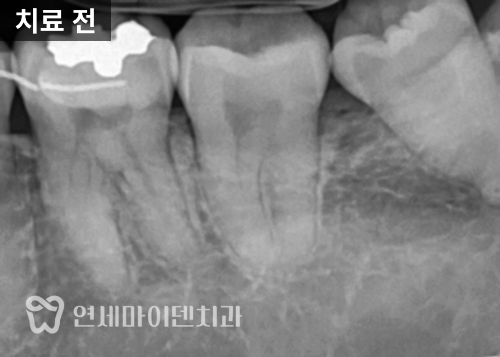

이번 케이스는 충치 치료 이후에도

시린 증상이나 씹을 때 통증이 지속된 케이스 입니다.

이런 경우 치아 크랙을 의심해볼 수 있는데요.

일반 엑스레이에서는

크랙이 잘 보이지 않기 때문에,

특수 광학 장비(Qray 등)를 활용해 찍어보았습니다.